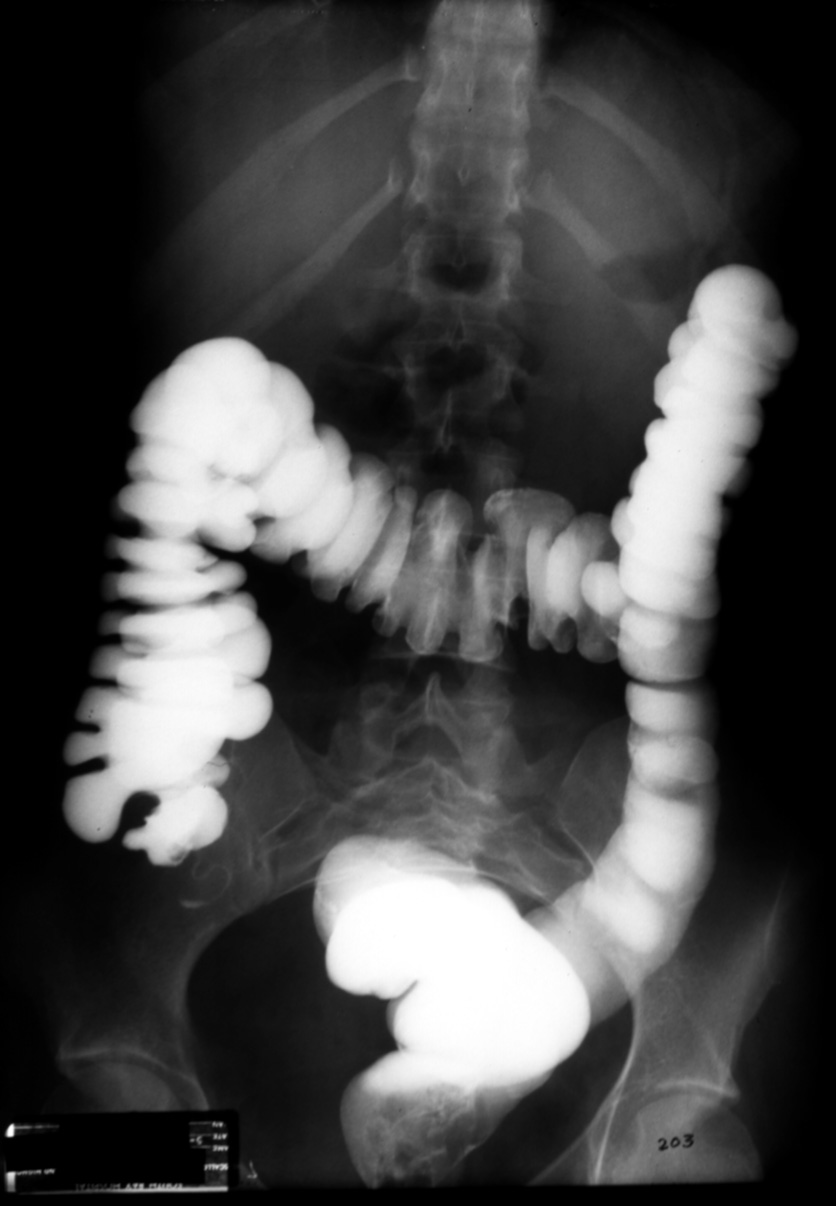

MS I 203 - Normal Barium Enema (BE)

Identify: rectum, sigmoid, descending colon, transverse colon, ascending

colon, cecum, appendix